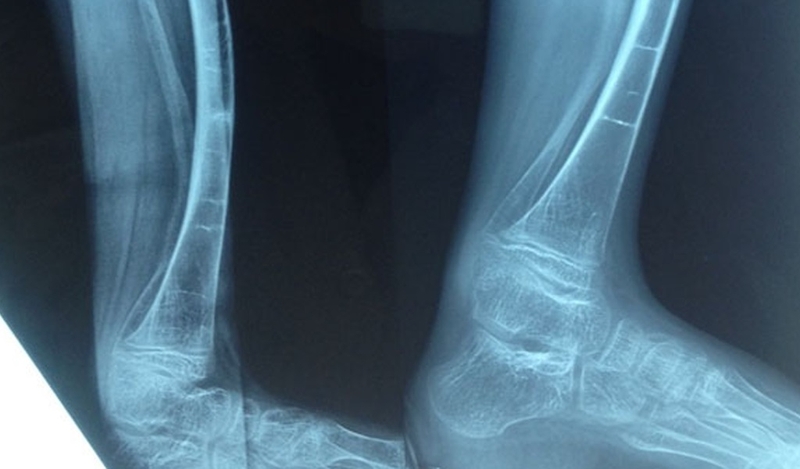

Bệnh nhân bị xương thủy tinh có khối lượng cơ bắp thấp, khớp và hệ dây chằng lỏng lẻo, khung xương giòn và dễ gãy. Triệu chứng nổi bật của bệnh này gồm: